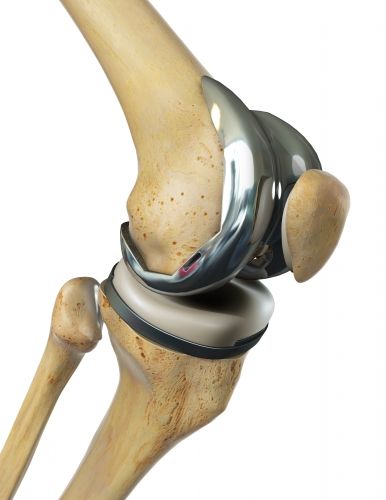

Die Knieendoprothese ist ein künstliches Kniegelenk. Sie soll die natürliche Knorpelgleitfläche des Kniegelenks ersetzen, um die Beweglichkeit wiederherzustellen. Dazu müssen künstliche Gleitflächen eingebracht werden. Die in einer Knieendoprothese gebräuchlichste Gleitfläche besteht aus Metall und Polyethylen. Als Metallkomponente dient meist eine Legierung aus Chrom, Kobalt und Molybdän. Diese Legierung kann Spuren von Nickel aufweisen, sodass im Falle einer Nickelallergie eine Metallprothese ohne Nickel gewählt wird.

Die Femurkomponente der Knieprothese aus Metall bedeckt das untere Ende des Oberschenkels im Kniegelenk. Sie muss die paarigen, walzenförmigen Enden des Oberschenkels (Femurkondylen bzw. Oberschenkelrollen) im künstlichen Kniegelenk exakt nachformen. Vorne in der Mitte zwischen den Femurkondylen weist die Femurkomponente einen Spalt bzw. eine Vertiefung auf. Diese entspricht der patellaren Gleitrinne (Trochlea), welche die Kniescheibe in sich aufnimmt. So kann die Kniescheibe stabil gleiten, während das Kniegelenk sich beim Gehen beugt und streckt.

Die Schienbeinkomponente bedeckt das Schienbeinplateau, auf dem der Oberschenkel im Kniegelenk gleitet. Kreuzband und Meniskus fixieren und stützen das Kniegelenk. Auch die Tibiabasisplatte (Schienbeinkomponente) besteht in der Regel aus Metall. Um der von oben kommenden Metallkomponente des Oberschenkels eine Gleitpaarung zu bieten, ist sie bedeckt durch eine elastische, aber haltbare Kunststoffschicht aus Polyethylen. Die Schienbeinkomponente kann durch einen Stiel im Knochen verankert werden, um ihre Haltbarkeit zu verbessern.

Wenn die Kniescheibe auf ihrer Rückseite durch eine Patellaarthrose geschädigt ist, kann eine Gleitfläche aus Polyethylen ihre Gleitfähigkeit wiederherstellen. Diese Kniescheibenkomponente muss nicht bei jeder Knie-TEP verwendet werden. Ist das Gelenk zwischen Kniescheibe und Oberschenkelknochen (Femoropatellargelenk) noch intakt, kann die natürliche Kniescheibe belassen werden.

Die Komponenten einer Knieprothese sind so aufgebaut, dass immer eine Metalloberfläche auf einer Kunststoffoberfläche gleitet (Gleitpaarung). Dies macht das künstliche Kniegelenk haltbarer und es nutzt nicht so schnell ab.